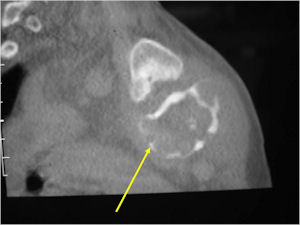

CT Scan:

- More useful for detecting mineralization and evaluating extent of bone destruction than plain X-ray

- The periosteum remains intact around the soft tissue component. Might need a CT scan to detect the subtle calcification (Egg Shell Rim of Calcification) associated with an intact periosteal reaction

- The lesion may be entirely radiolucent but usually shows some degree of mineralization. Mineralization may appear stippled like cartilage but do not see chondroid pathologically. Mineralization is sometimes better detected on a CT scan rather than an x-ray.